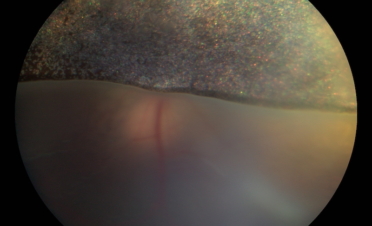

Ojos de Fox a su llegada al IVO con ceguera aguda por desprendimento de retina. Fotos: IVO

La retinografía permite, a modo de fotografía, obtener imágenes en color de la retina. Es una prueba que proporciona una información muy valiosa sobre el estado de la retina y el nervio óptico.

En ambas pruebas se observaron imágenes compatibles con un desprendimiento de retina:

Retinografías de Fox, un perro de raza Pomerania con desprendimiento de retina en ambos ojos. Foto: IVO. (Clicar la fotografía para ampliar).